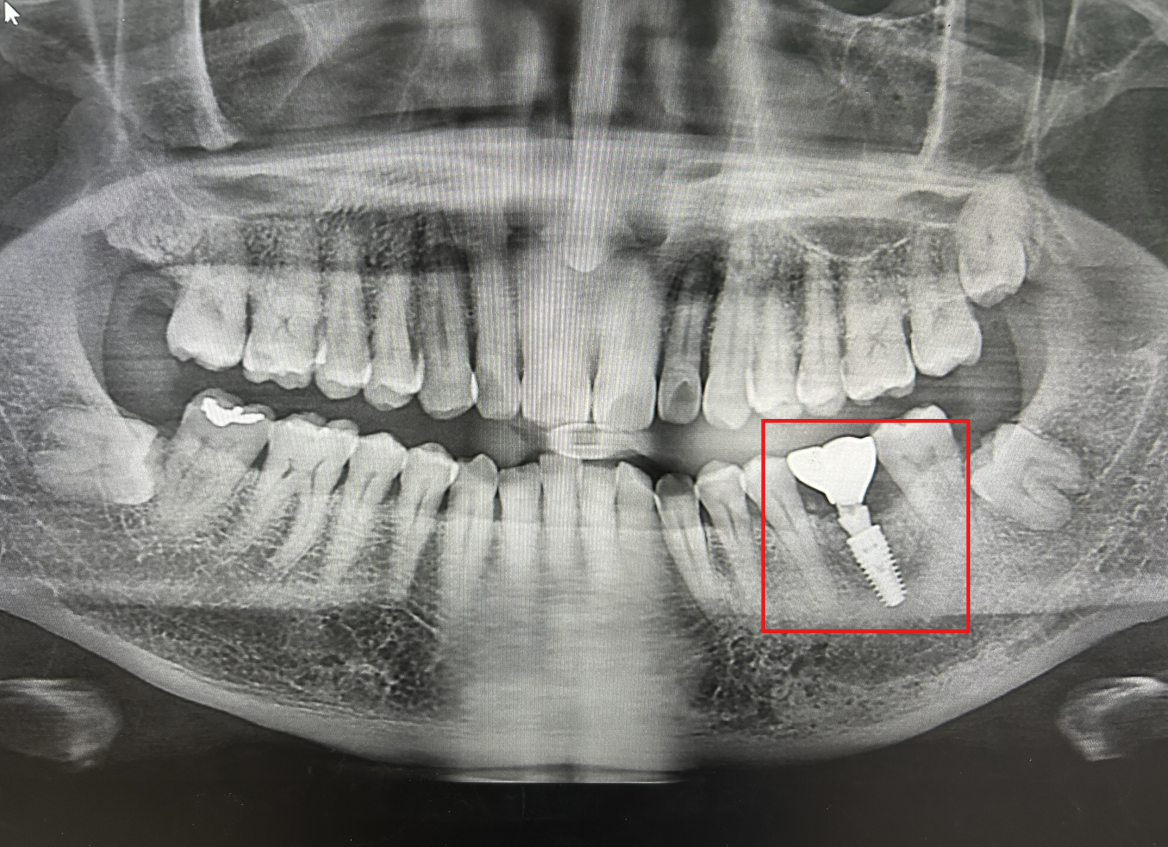

[사진·영상·이미지 한컷] 임플란트 1년 후...'이상 無'

History 2023년 12월 -  치아 제거 수술2024년 06월 - 골 유착 및 융합  (골유착률)2024년 07월 - 나사와 치아 심기 (식립성공률)2025년 03월 - 이상유무검사(파절저항성) 독일'의 정밀 기술!  이미지 속성    P.S.  만 65세 이상은 2개(?) 건강보험적용 된다.   난 내 돈 거금 주고... ㅠㅠ  잇몸과 이빨관리 잘하자!